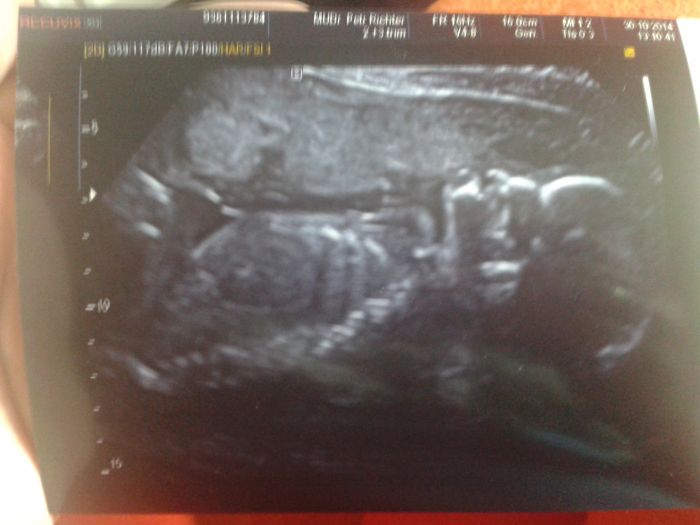

Holky tak genetika dopadla na výbornou a moje tušení se vyplnilo, bude to holčička :) je nas tu se slecnama většina že :)

Děkuji pěkně :) ještě přidám fotku :)